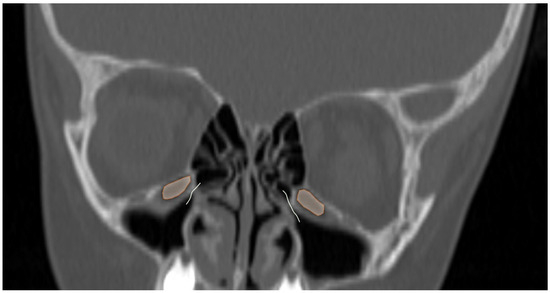

Comparison of Two Methods for Assessing the Maxillary Sinus Volume in Patients with and Without Unilateral Cleft Lip and Palate: A Retrospective Cross-Sectional Study

Background/Objectives: The aim of this study was to compare two methods for maxillary sinus volume measurement, assessing their accuracy. The analysis compared the maxillary sinus volume in patients with unilateral cleft lip and palate (UCLP) and in a non-cleft group, using a manual method and a three-dimensional (3D) semi-automated segmentation method. Methods: The research was conducted according to the STROBE guidelines. Sixty patients were included in this study: thirty patients with UCLP were in the research group, and the control group consisted of 30 patients with no craniofacial deformities. Cone-beam computed tomography (CBCT) was analyzed. The manual maxillary sinus volume was calculated based on its approximation to two geometric shapes based on mathematical formulas using linear measurements that were performed on all sinus CBCT scans in the maximum diameter in three planes. The semi-automatic segmentation method using ITK-SNAP 3D-imaging software version 4.2.2 was used to automatically calculate the maxillary sinus volume of the sinuses. The manually calculated volume was compared with the automatically calculated one, and statistical analysis was performed. Results: The cleft group presented lower values in both the automatic and manually calculated volumes for both the right (automatic: p = 0.49; manual p = 0.009) and left (automatic: p = 0.46; manual p = 0.11) maxillary sinuses than the non-cleft group. The cleft group presented statistically significant higher discrepancies in values between the manual and semi-automatic method than the control group (RMSV p = 0.0011; LMSV p = 0.033; TMSV p = 0.003). Conclusions: The manual method may not reveal the exact anatomical topography of the maxillary sinuses. In UCLP patients, the maxillary sinus anatomy may be more complex. Therefore, a semi-automated method may be more advisable to preserve the accuracy of the measurements. Full article

Show Figures

Figure 1